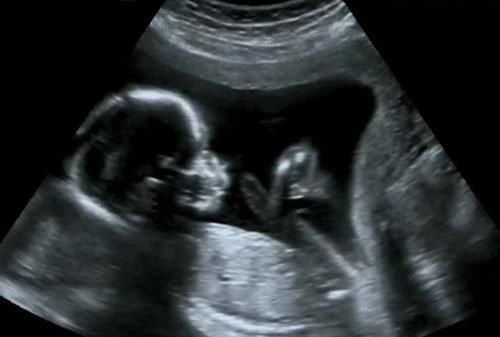

【 彩超|做四维医生说腹部脂肪厚,看不清,打出来单子也只能看宝宝大概面部怎么办?】一.彩超看胎儿的原理是什么?我们通常看胎儿使用二维彩超就可以了,这种彩超技术看胎儿的原理就是把所见到的影像形成一个切面,呈现出一个平面展现出来,非常直观,胎儿主要看胎儿的四肢和身体结构使用二维彩超即可以看见。现在的二维彩超在平面技术的基础上加上了血流信号的显示,就是我们经常去做的多普勒超声检查,在妇产科主要看胎儿脐血流,心脏血流情况,通过血流信号可以判断胎儿血流供应情况。

二.肚皮太厚,胎儿看不清怎么办?肚皮的厚度就像墙壁一样,超声的原理就是声波的穿透性,如果肚皮越厚,也声波越难以通过,在彩超机器上就难以显示出来。如果你看的是羊水量,脐血流其实影响不大,因为血流信号一般都能显示出来;如果看的是胎儿身体结构,则肚皮厚度超过5cm以上的孕妇则很难看清。此时磁共振是解决肚皮厚照不到胎儿的有效解决办法。